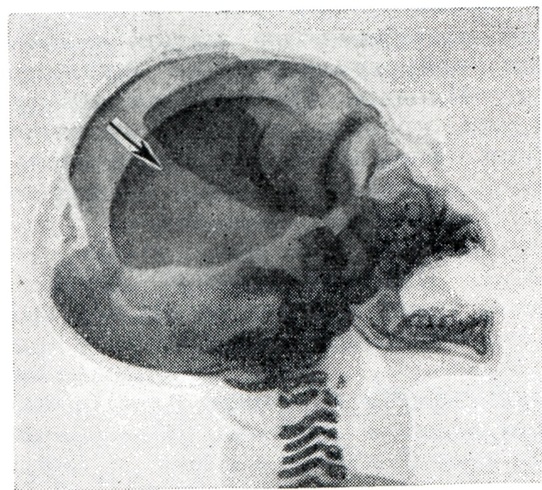

Костный скелет плода при Внутриутробная смерть характеризуется изменившимся по сравнению с нормой положением отдельных частей скелета и неправильными взаимоотношениями костей черепа, позвоночника и конечностей; в костях черепа происходят такие изменения, как черепицеобразное захождение краёв костей друг за друга (рисунок 1), уменьшение вследствие этого размеров черепа, расхождение костей со ступенчатым смещением одной кости по отношению к соседним, деформация черепа (уплощение свода или мешкообразная вытянутость формы).

Рис. 1.

Резкое смещение теменной кости вниз и вперёд (указано стрелкой) при внутриутробной смерти плода; рентгенограмма.